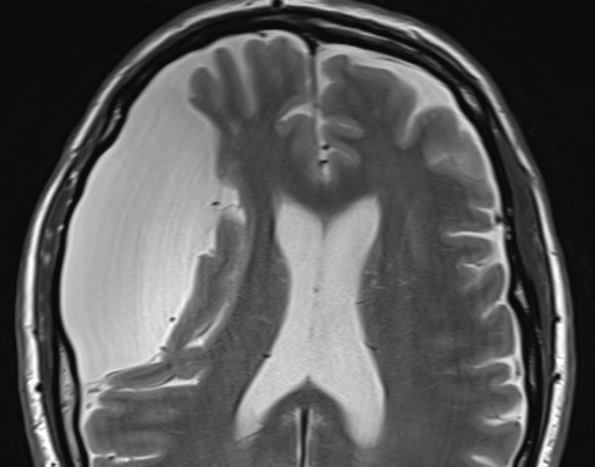

Kyste Colloïde du 3e Ventricule

- Obstruction du foramen de Monro → Hydrocéphalie Obtructive

- Clinique typique: Hydrocéphalie posturale (Effet yoyo obstructif de la masse)

- Hypersignal T1, Hypo T2 (protéines)

- Hyperdense au CT